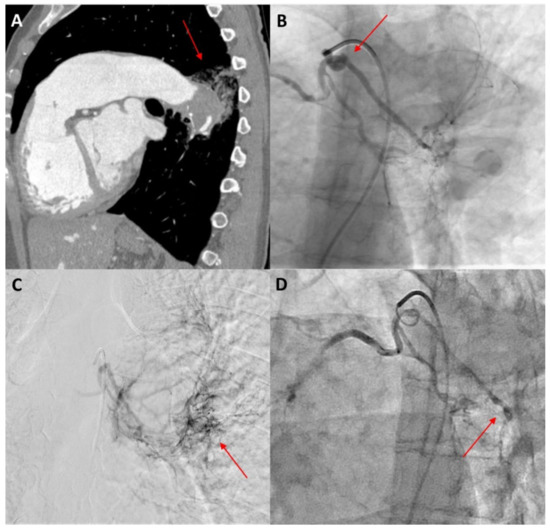

5.4. Bronchial Artery Embolization

- Rasciti, E.; Sverzellati, N.; Silva, M.; Casadei, A.; Attinà, D.; Palazzini, M.; Galiè, N.; Zompatori, M. Bronchial Artery Embolization for the Treatment of Haemoptysis in Pulmonary Hypertension. Radiol. Med. 2017, 122, 257–264. [Google Scholar] [CrossRef]

- Mamas, M.A.; Clarke, B.; Mahadevan, V.S. Embolisation of Systemic-to-Pulmonary Collaterals in Patients with the Eisenmenger Reaction Presenting with Haemoptysis. Cardiol. Young 2008, 18, 528–531. [Google Scholar] [CrossRef]